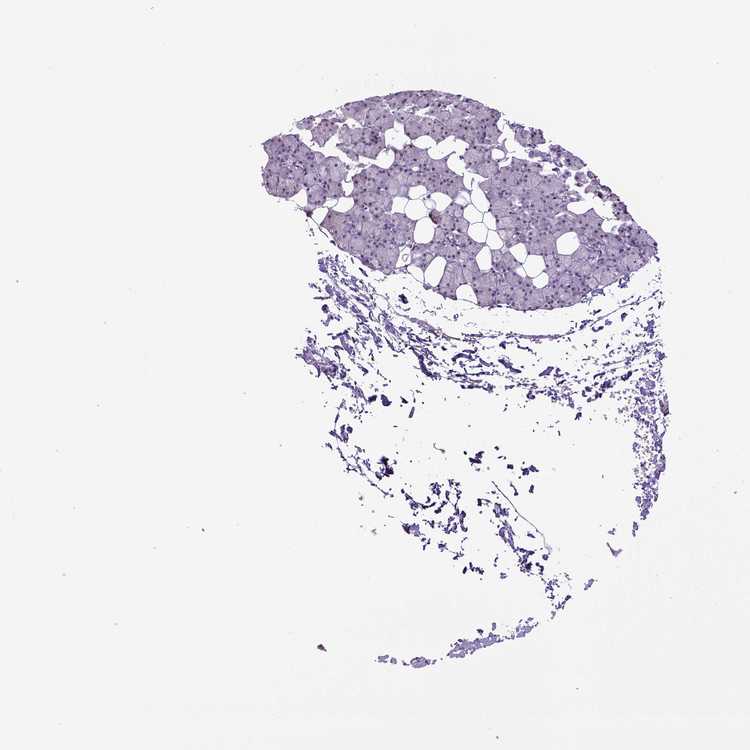

Female, age 68

Salivary gland sample 216

nTPM: 18.4

Cell types%

Glandular cells:

45

Ductal cells:

25

Adipocytes:

5

Other cell types: